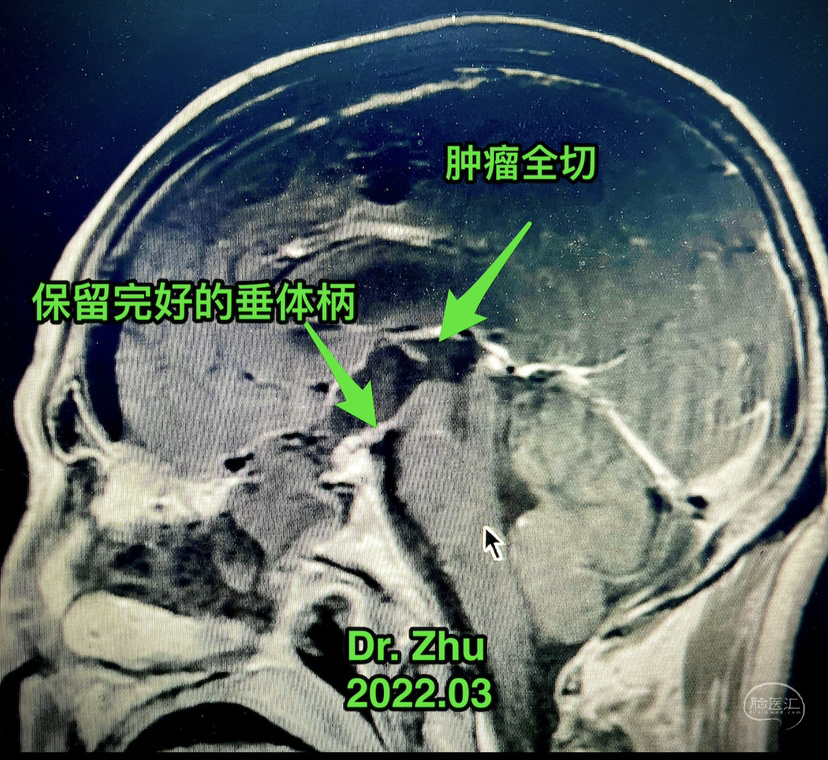

术后

术后72小时